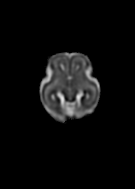

Fetal cortical plate segmentation is essential in quantitative analysis of fetal brain maturation and cortical folding. Manual segmentation of the cortical plate, or manual refinement of automatic segmentations is tedious and time-consuming. Automatic segmentation of the cortical plate, on the other hand, is challenged by the relatively low resolution of the reconstructed fetal brain MRI scans compared to the thin structure of the cortical plate, partial voluming, and the wide range of variations in the morphology of the cortical plate as the brain matures during gestation. To reduce the burden of manual refinement of segmentations, we have developed a new and powerful deep learning segmentation method. Our method exploits new deep attentive modules with mixed kernel convolutions within a fully convolutional neural network architecture that utilizes deep supervision and residual connections. We evaluated our method quantitatively based on several performance measures and expert evaluations. Results show that our method outperforms several state-of-the-art deep models for segmentation, as well as a state-of-the-art multi-atlas segmentation technique. We achieved average Dice similarity coefficient of 0.87, average Hausdorff distance of 0.96 mm, and average symmetric surface difference of 0.28 mm on reconstructed fetal brain MRI scans of fetuses scanned in the gestational age range of 16 to 39 weeks. With a computation time of less than 1 minute per fetal brain, our method can facilitate and accelerate large-scale studies on normal and altered fetal brain cortical maturation and folding.